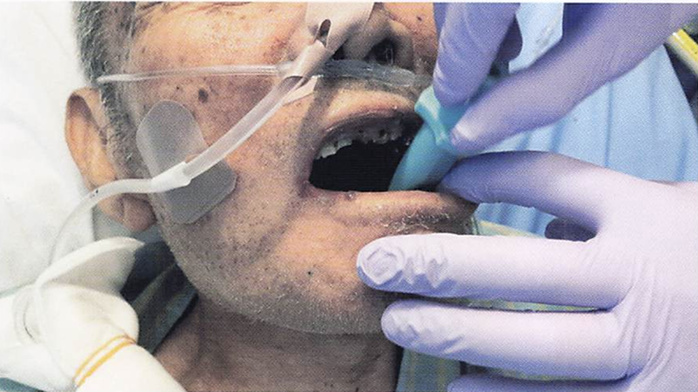

午前-87

80歳の男性。5年前に脳梗塞を発症し、現在在宅療謹中で、意識障害があるという。口臭が強いことを主訴として家族から歯科訪問診療の依頼を受けた。 歯科医師から口腔衛生管理を指示きれた。口腔清掃時の写真を別に示す。この患者に行うのはどれか。2つ選べ。

a.頭部の後屈

b.歯の動揺の確認

c.ラポールの形成

d.リクライニング位の設定

解答を見る

b.d